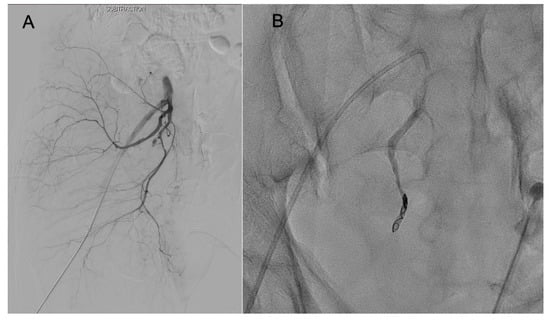

| Age | Sex | Mechanism | SBP (Initial/Worst) (mmHg) | SBP Recovered After REBOA (mmHg) | PR (/min) | ISS | YB Classification | Time from REBOA Insertion to Removal | Time from REBOA Inflation to Deflation | Location of REBOA Ballooning | AE Details | Embolized Artery | Transfusion Amount ≤ 24 h (Packed RBC) | ICU Stay | HS | Complication | Mortality |

|---|---|---|---|---|---|---|---|---|---|---|---|---|---|---|---|---|---|

| 57 | M | TA | 80/68 | 95 | 102 | 38 | LC2 | 220 | 51 | Zone III | Unilateral selective | IIA branch | 8 | 10 | 52 | Pneumonia | No |

| 70 | M | TA | 64/54 | 88 | 88 | 25 | APC3 | 740 | 38 | Zone III | Bilateral selective | IIA branch | 9 | 15 | 23 | Atelectasis | No |

| 74 | F | Pedestrian accident | 81/73 | 100 | 88 | 22 | LC1 | 57 | 14 | Zone III | Bilateral selective | IIA branch | 2 | 3 | 10 | No | No |